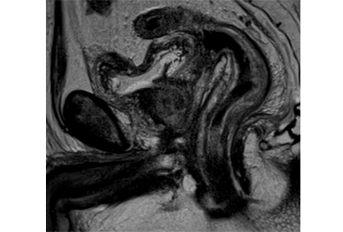

The use of multiparametric magnetic resonance imaging (mp-MRI) for prostate cancer has increased over recent years, mainly for detection, staging, and active surveillance. However, suspicion of recurrence in the set of biochemical failure is becoming a significant reason for clinicians to request mp-MRI. Radiologists should be able to recognize the normal post-treatment MRI findings. Fibrosis and atrophic remnant seminal vesicles after prostatectomy are often found and must be differentiated from local relapse. Moreover, brachytherapy, external beam radiotherapy, cryosurgery, and hormonal therapy tend to diffusely decrease the signal intensity of the peripheral zone on T2-weighted images (T2WI) due to the loss of water content, consequently mimicking tumor and hemorrhage. The combination of T2WI and functional studies like diffusion-weighted imaging and dynamic contrast-enhanced improves the identification of local relapse. Tumor recurrence tends to restrict on diffusion images and avidly enhances after contrast administration either within or outside the gland. The authors provide a pictorial review of the normal findings and the signs of local tumor relapse after radical prostatectomy, external beam radiotherapy, brachytherapy, cryosurgery, and hormonal therapy.